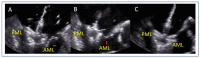

Mitral regurgitation (MR) is a common valvular heart disease associated with significant morbidity and mortality. For patients at high or prohibitive surgical risk, mitral transcatheter edge-to-edge repair (M-TEER) offers a less invasive alternative to surgery. This review outlines key aspects of patient selection and procedural planning for M-TEER, with a focus on clinical and echocardiographic criteria essential for success. Comprehensive imaging-especially 2D and 3D transesophageal echocardiography-is critical to assess leaflet anatomy, coaptation geometry, and mitral valve area. Selection criteria differ between primary and secondary MR and are guided by trials such as COAPT and MITRA-FR. Optimal outcomes rely on careful screening, anatomical suitability, and multidisciplinary evaluation. With growing experience and advancing technology, M-TEER has become a transformative option for treating severe MR in non-surgical candidates.